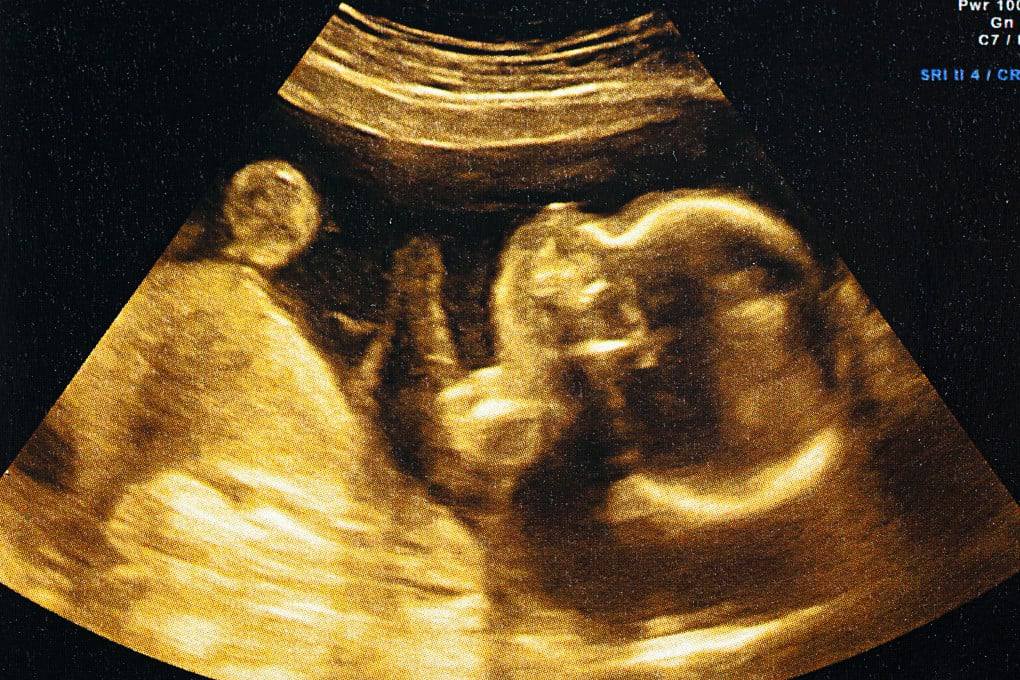

Китайские исследователи впервые в мире смогли воспроизвести процесс внедрения человеческого эмбриона в стенку матки в лабораторных условиях.

В ходе эксперимента ученые использовали модель эмбриона, созданную на основе стволовых клеток человека, а также искусственную ткань, имитирующую слизистую оболочку матки. Это позволило в реальном времени наблюдать, как эмбрион прикрепляется к поверхности и начинает проникать в тканевые структуры.

В естественной среде имплантация происходит на раннем этапе беременности и остается недостаточно изученной из-за этических и технических ограничений, что затрудняет детальное исследование этого процесса.